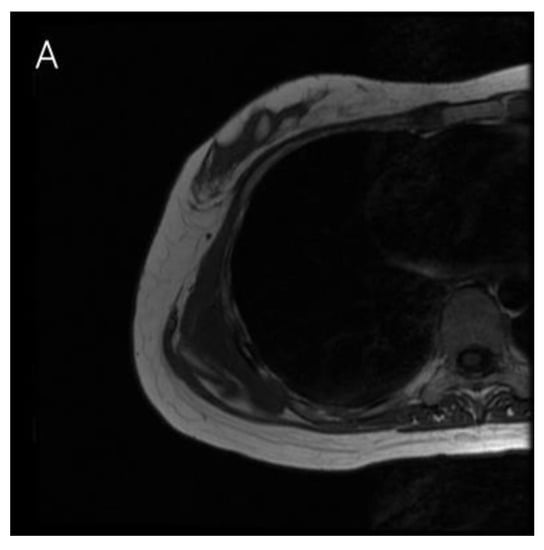

2. Case Presentation